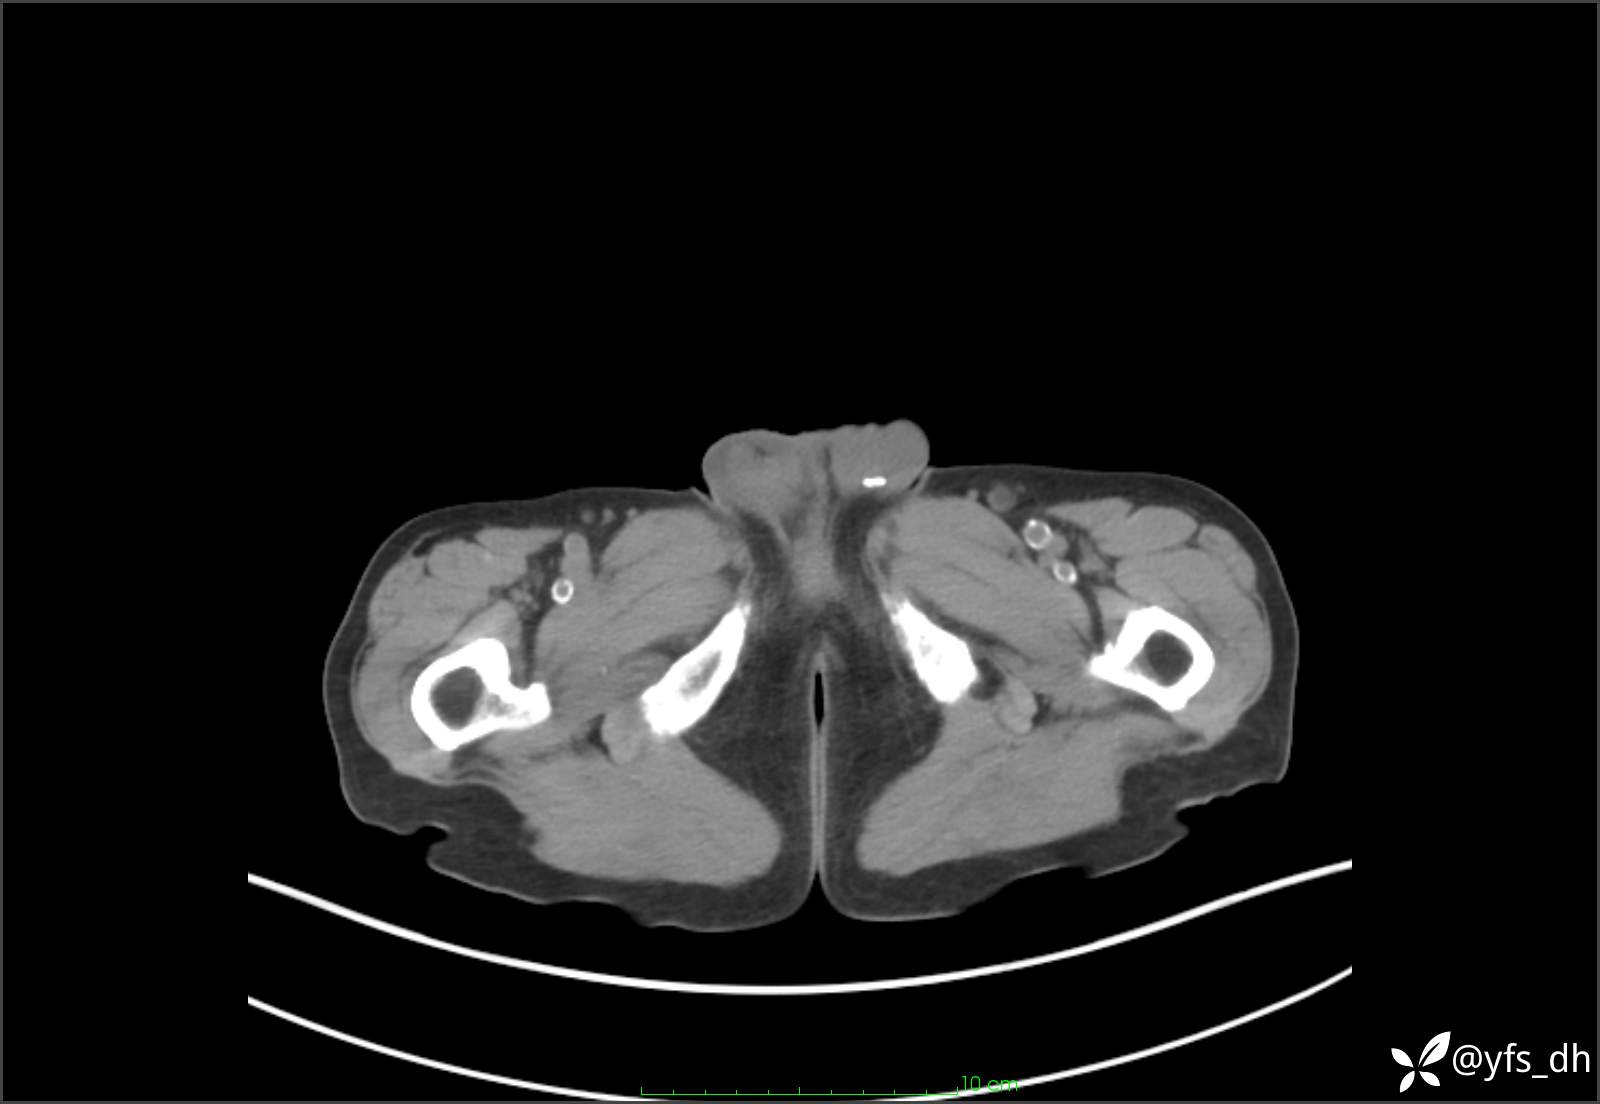

1.简要病史:患者4天前突发上腹部疼痛不适,但可以忍受。3小时前饭后突然加重,不能忍受后就诊。

2.简要手术记录:术中见腹盆腔大量肠液及粪便,乙状结肠中下段见一约3cm的破口。